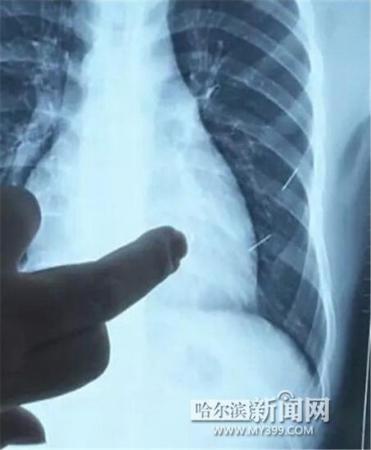

醫(yī)生指出X光片上的針狀物

昨日上午,記者在哈醫(yī)大二院第八住院部心外三病房找到了躺在病床上痛苦不堪的董立仁,家屬正在他身旁不斷安慰著他。見記者前來,董立仁母親李百燕拿出一張X光片,上面可以清晰地看到胸腔內(nèi)一共有4根針狀物,其中一根在心臟部位,兩根在胸腔壁上,還有一根在腹腔壁上。

心外三病房董立仁的主治醫(yī)生告訴記者,董立仁送到醫(yī)院時病情很危險,隨時可能危及生命。“通過檢查發(fā)現(xiàn),他心臟內(nèi)有一個金屬異物,正好在心臟上。心臟每次跳動都與其產(chǎn)生摩擦,導致出血,心包積液懷疑是血液。如果大量出血會凝結(jié)成血塊,血塊包裹住心臟就會影響心臟跳動,隨時都有停跳的危險。心臟上的異物是致命傷,其余胸腔壁和腹腔壁的異物傷害不大。”

昨天16時30分左右取針手術(shù)開始。因鋼針隨時會危及患者生命,此次手術(shù)定義為大型手術(shù)。開胸后,醫(yī)生打開董立仁心包,發(fā)現(xiàn)一枚鋼針已深深扎入心臟,僅露出1厘米長度在外。拔出鋼針后,醫(yī)生發(fā)現(xiàn),這枚針長達5厘米。受鋼針影響,心包出現(xiàn)大量積液,近800毫升。

隨后,在下胸壁位置,第二枚鋼針順利取出。在尋找另兩枚鋼針過程中,普外、胸外多名醫(yī)生也參與手術(shù),為主刀醫(yī)生提供更為穩(wěn)妥的處理建議。根據(jù)X光片顯示位置,醫(yī)生未在患者體內(nèi)找到剩余兩枚鋼針。醫(yī)生懷疑,其中一枚鋼針可能深藏在肋骨骨膜位置,無法尋找,最后決定結(jié)束手術(shù),做進一步觀察,研究下一次手術(shù)方案。